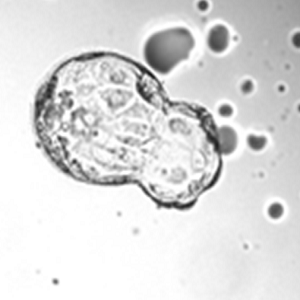

A hatching human blastocyst that developed in SYNBIOS® SYNTHETIC EMBRYO CULTURE MEDIUM. Image was captured using the embryoscope. The hatching occurred following laser assisted hatching. The workers perform routine laser assisted hatching on day 3 for 80% of their patients because their treatment SOP is to perform biopsy on day 5-7.

Courtesy: Yousef AlHelou, April 2020, Fakih IVF, United Arab Emirates.